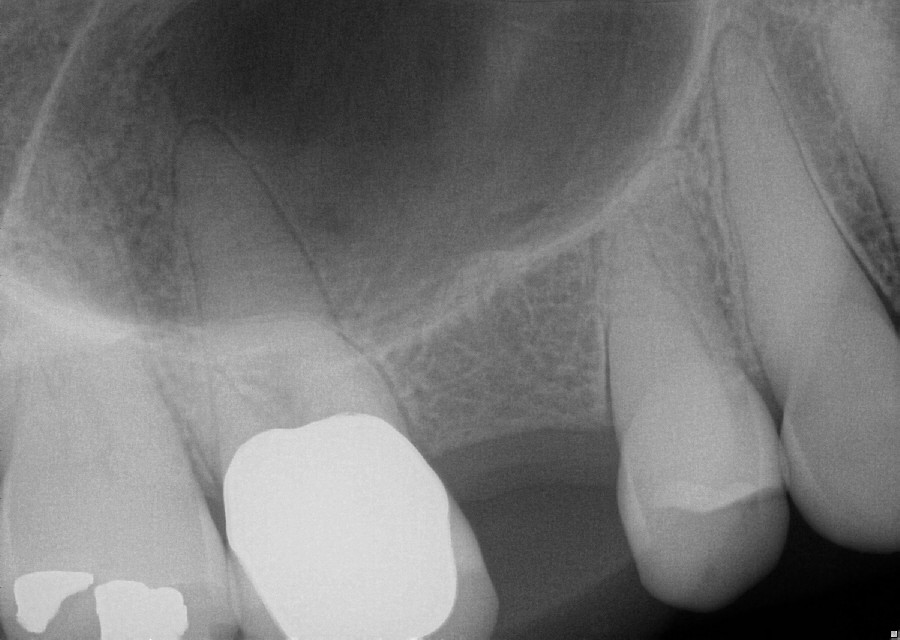

Sinus Lifts Charles D. Payet, DDS, PA